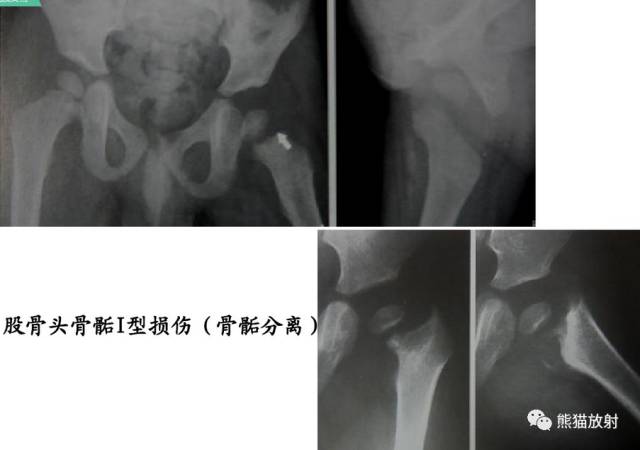

I型:骨骺分离(有或无移位,多不引起生长障碍)

第一型(Ⅰ型) 骨骺分离,分离一般发生在生长板的肥大层,故软骨的生长带留在骨骺一侧,所以多不引起生长障碍;婴幼儿骺板软骨层较宽,容易发生骨骺分离,据统计,占骨骺损伤的15.9%;唯一的x线征象是骨化中心移位,该型复位容易,预后良好;而股骨头骨骺分离由于骨骺动脉多被破坏,预后不佳。该型也可见于坏血病、佝偻病、骨髓炎和内分泌疾病所致的病理性损伤。